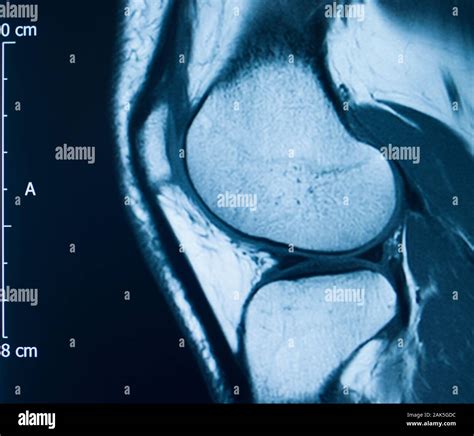

An Mcl Tear Mri is a non-invasive imaging technique that provides detailed images of the knee joint. MRI uses magnetic fields and radio waves to create cross-sectional images of the body’s internal structures. This allows healthcare professionals to visualize the MCL and other soft tissues in the knee, identifying any tears or damage.

During an *Mcl Tear Mri*, the patient lies on a table that slides into a large, cylindrical machine. The procedure is painless and typically takes about 30-60 minutes. The MRI machine captures multiple images from different angles, providing a comprehensive view of the knee joint.

An *Mcl Tear Mri* is particularly useful for differentiating between an MCL tear and other knee injuries, such as meniscal tears or anterior cruciate ligament (ACL) injuries. This information is crucial for developing an appropriate treatment plan.